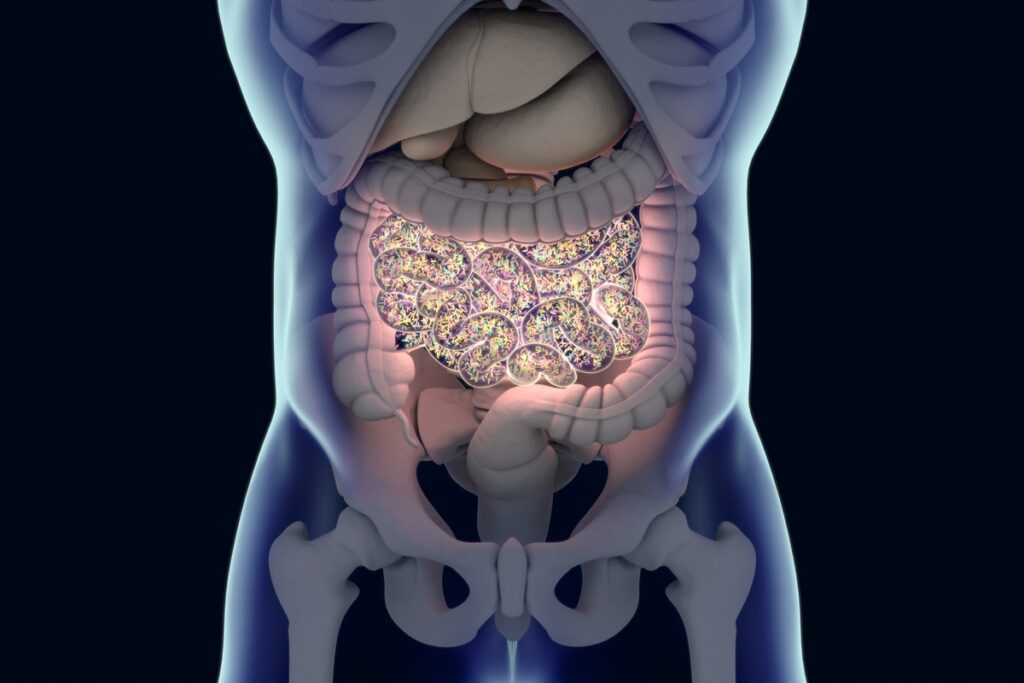

A microbiota intestinal é composta por cerca de 4,5 mil tipos diferentes de bactérias que trabalham juntas para manter as funções corporais. Quando esse sistema se desequilibra, aumentam os riscos de problemas de saúde relacionados à digestão, regulação do peso, sistema imunológico e saúde mental.